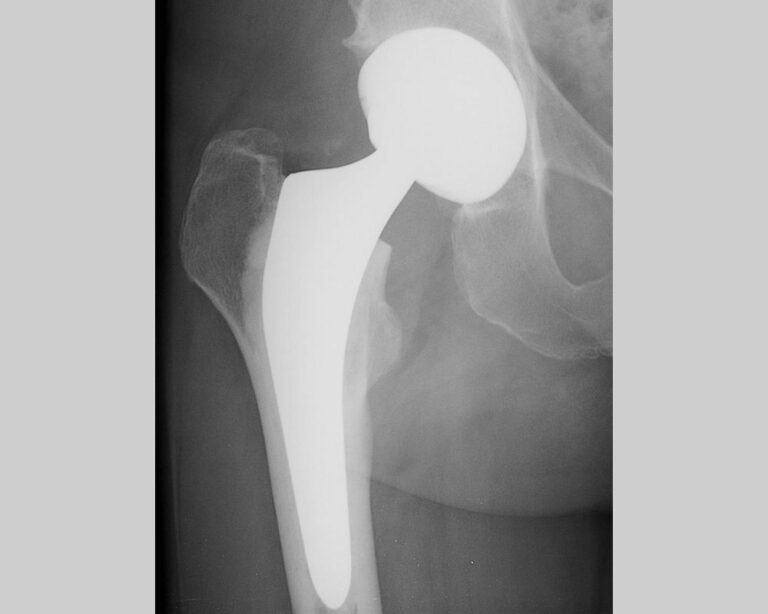

Premium Photo Total hip arthroplasty, xray image very good quality Total Hip Replacement Surgery Anaesthesia What is the best option for total hip or knee replacement? The two main types of anesthesia used for hip replacement or knee replacement surgery are regional anesthesia and general anesthesia. Types of anaesthetic for a hip or knee replacement. You are going to have a hip or knee replacement. 2 observational studies have suggested that spinal. Total hip arthroplasty. Total Hip Replacement Surgery Anaesthesia.